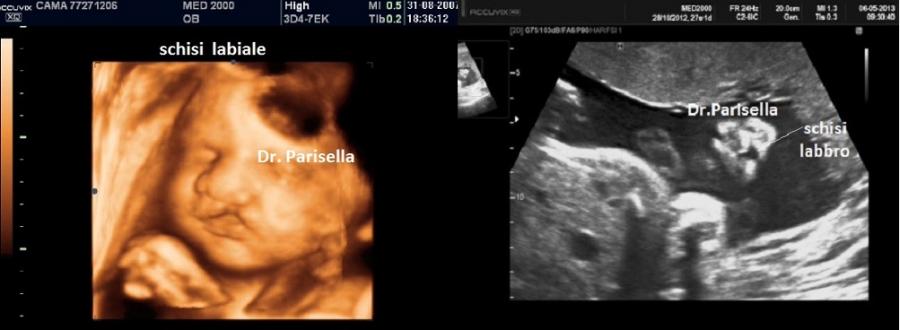

2) labioschisi con o senza palatoschisi;